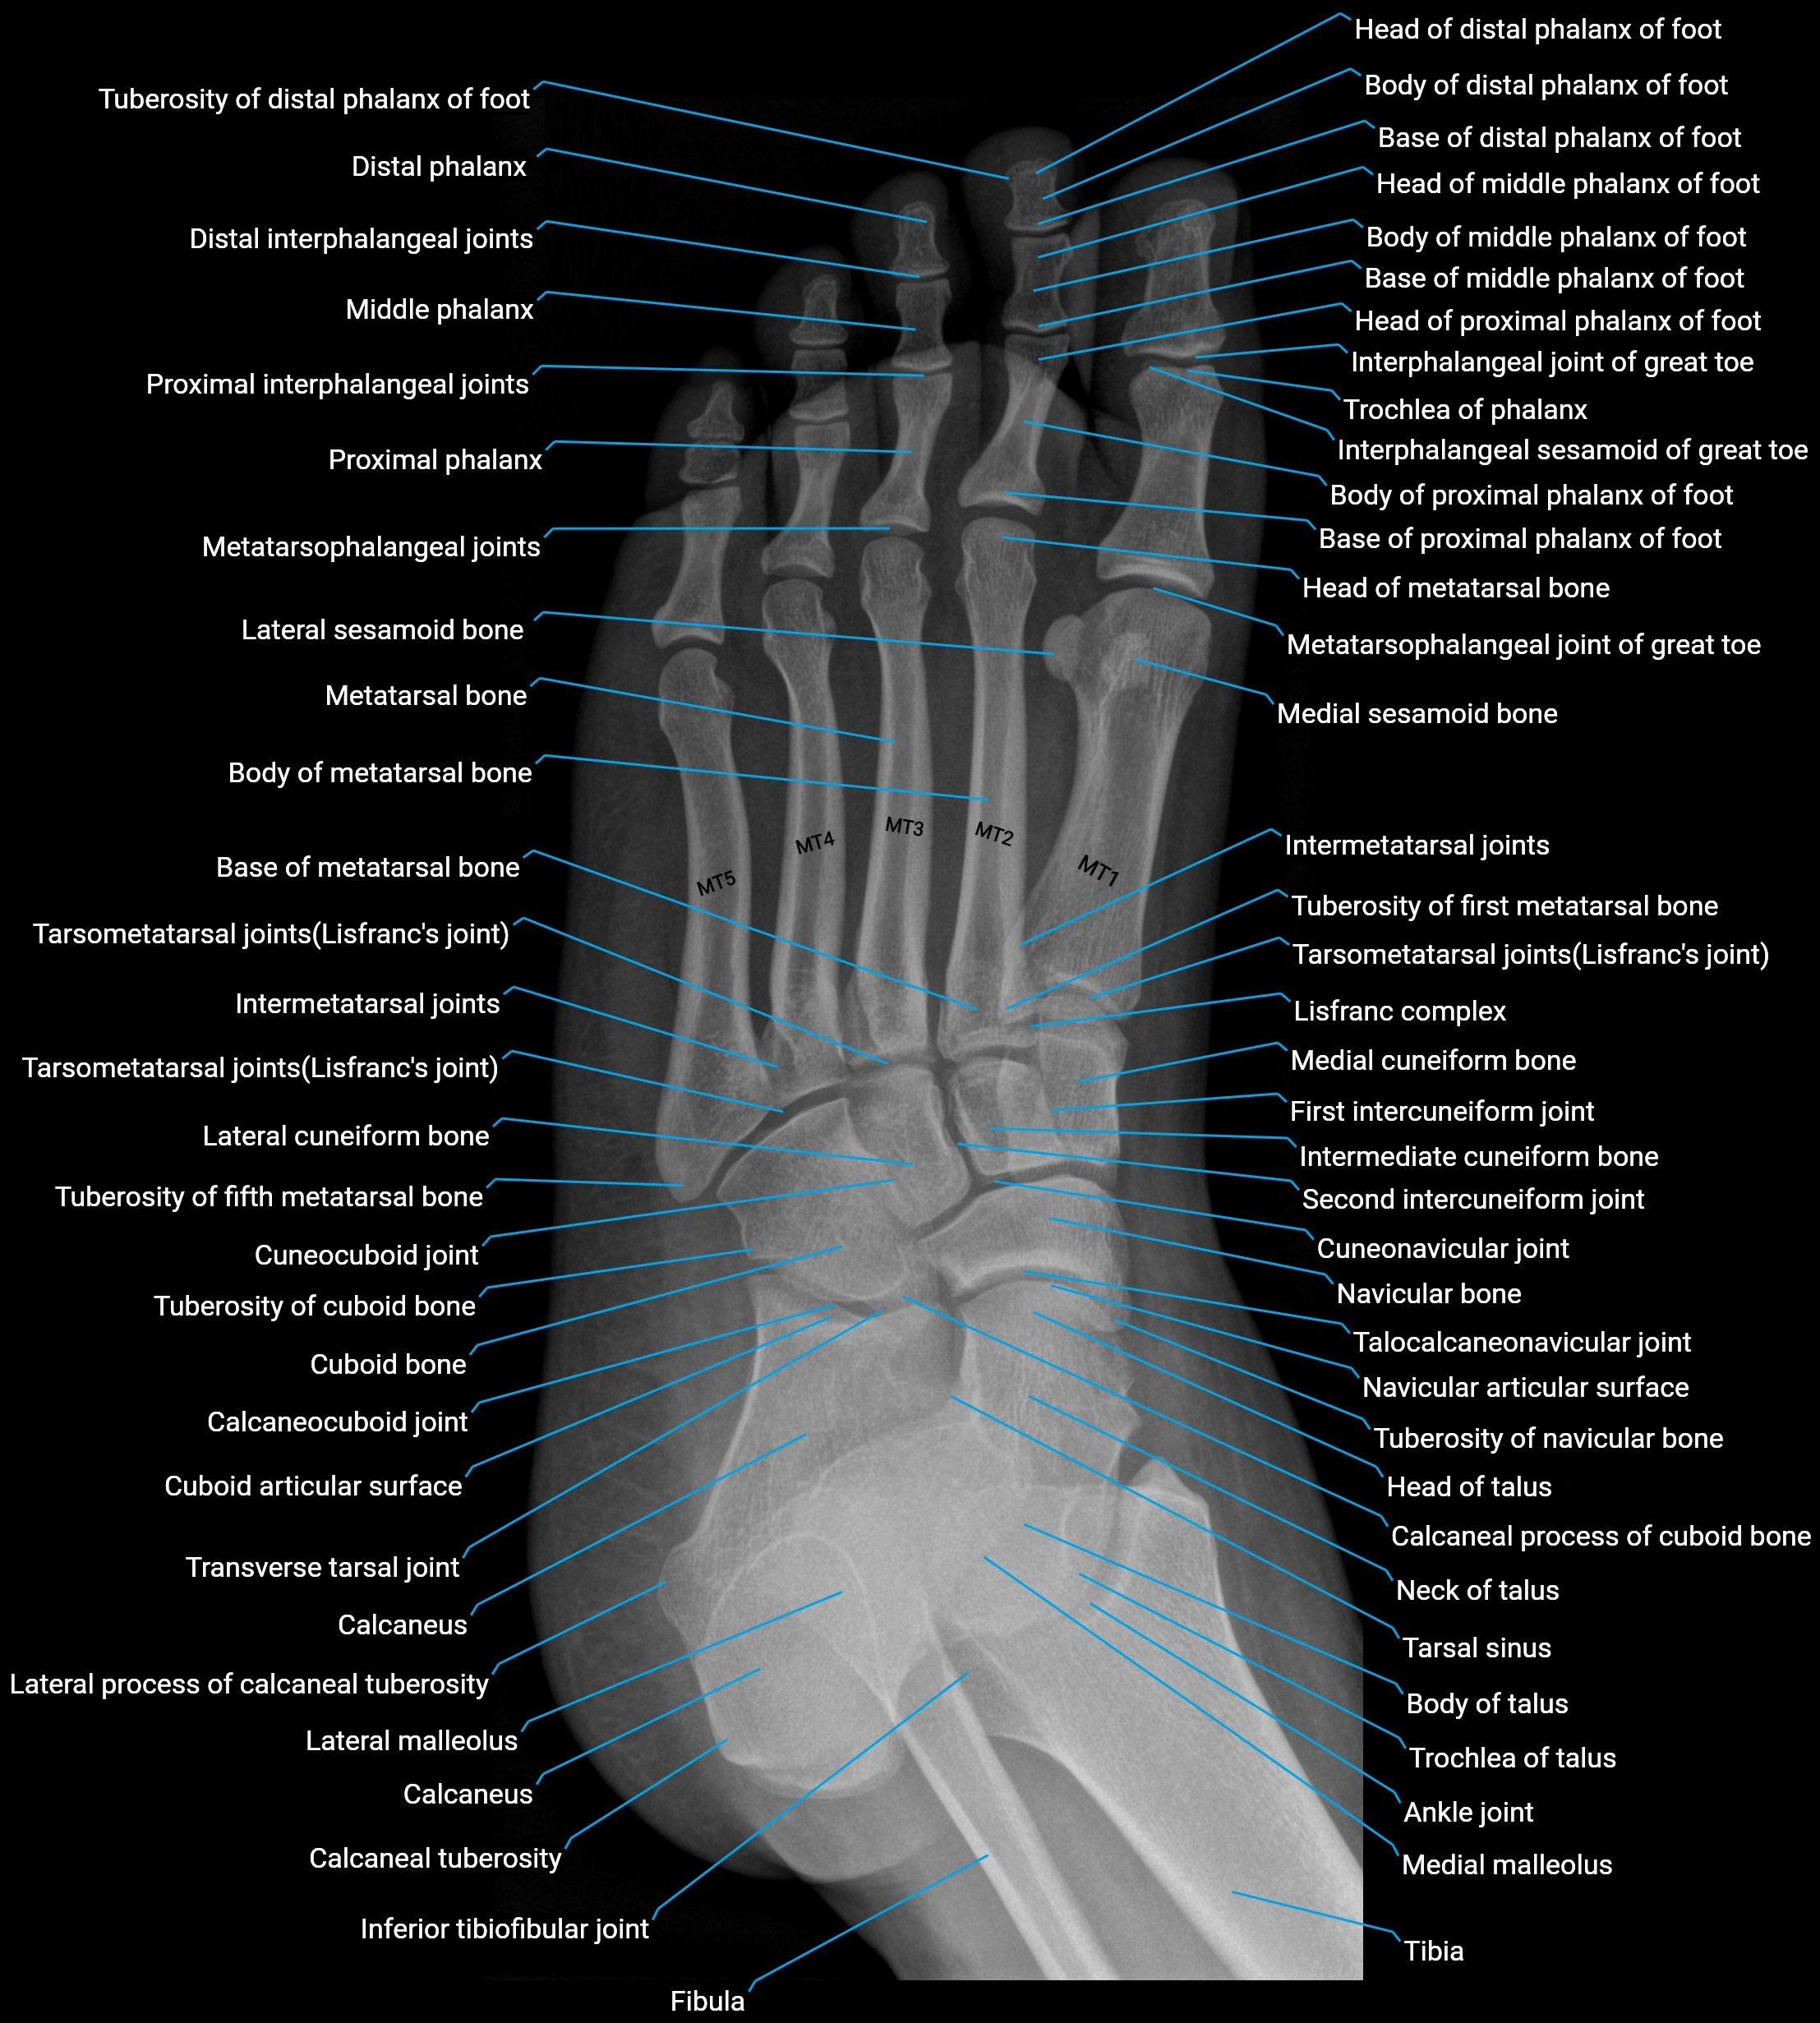

- Ankle joint

- Calcaneus

- Fibula

- Inferior tibiofibular joint

- Intermetatarsal joints

- Interphalangeal joint of great toe

- Interphalangeal sesamoid of great toe

- Lateral malleolus

- Lateral process of calcaneal tuberosity

- Lateral sesamoid bone

- Lisfranc complex

- Medial cuneiform bone

- Medial malleolus

- Medial sesamoid bone

- Metatarsal Bones (MT)

- Metatarsophalangeal joint of great toe

- Metatarsophalangeal joints

- Navicular bone

- Neck of talus

- Second intercuneiform joint

- Talocalcaneonavicular joint

- Tarsal sinus

- Tarsometatarsal joints

- Tibia

- Transverse tarsal joint

- Trochlea of talus

- Tuberosity of fifth metatarsal bone

- Tuberosity of first metatarsal bone

- Tuberosity of navicular bone